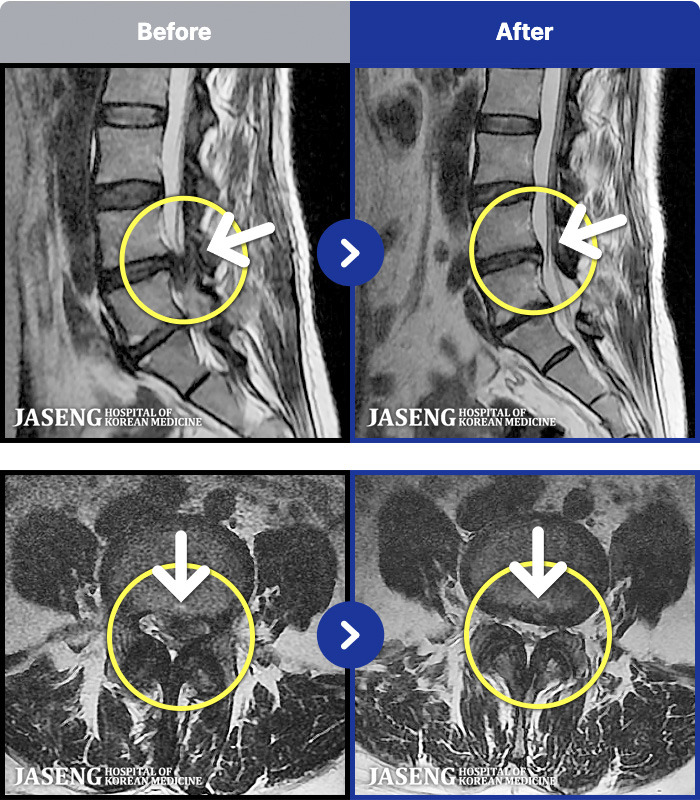

1,293 MRI ũ ʸ Ȯϼ.